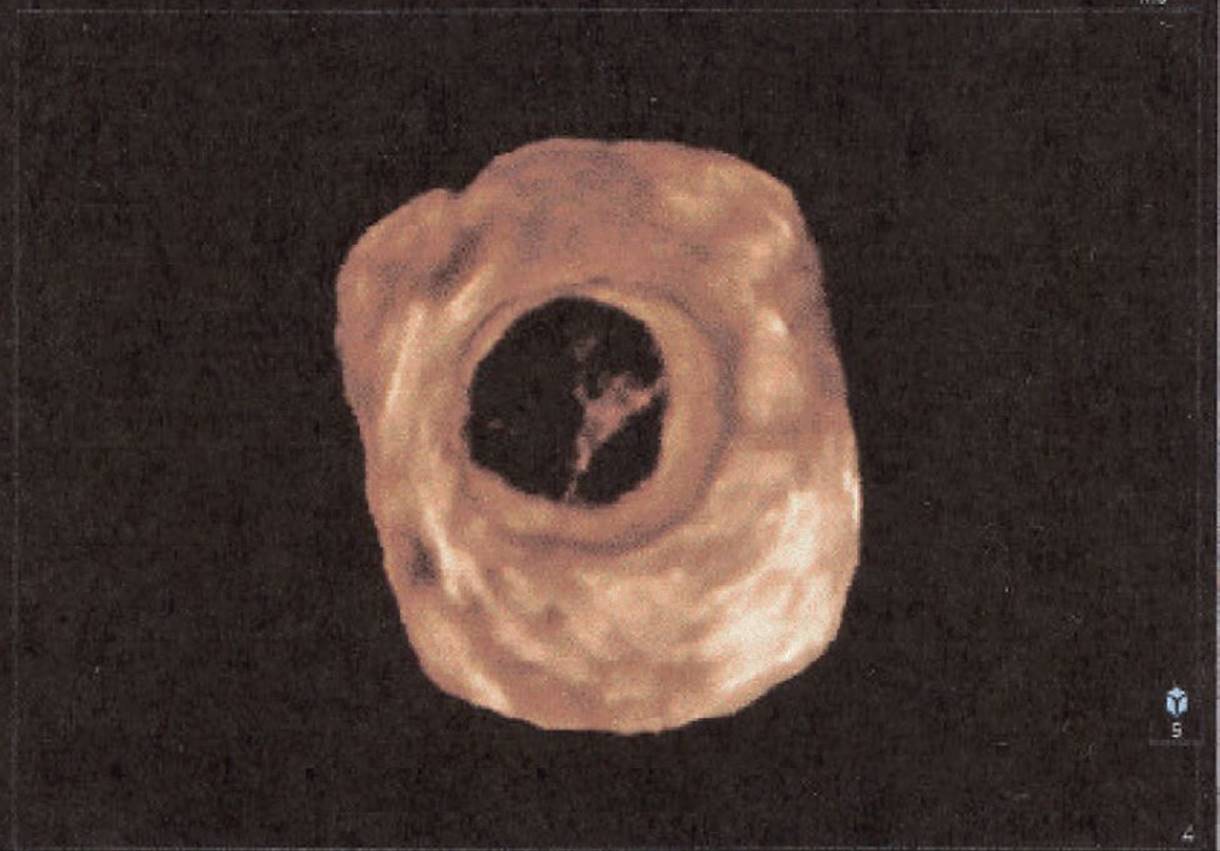

Three-dimensional sonography has many clinical applications in gynecologic disorders (Figs. 8–28 through 8–37). As in obstetrical 3D, gynecologic 3D affords depiction of the uterus and ovaries in any selectable scan plane, including those not readily obtained with 2D. These include improved depiction of endometrial masses such as polyps or submucosal fibroids, improved localization and calculation of changes in fibroid volume, enhanced depiction of tubal masses, intrauterine device localization, and uterine malformations. Three-dimensional depiction of tumor morphology and vascularity within ovarian masses has important implications in distinguishing benign from malignant masses.

Because of its ability to display in the coronal plane, 3D sonography is accurate in depicting intraluminal masses such as polyps or fibroids. The location of an intrauterine contraceptive device (IUCD) within the endometrium is readily depicted with 3D sonography. Three-dimensional sonography obtained in the transverse plane of the uterus fundus is also useful in identifying tubal masses since their origins can be traced to the cornual area of the uterus.